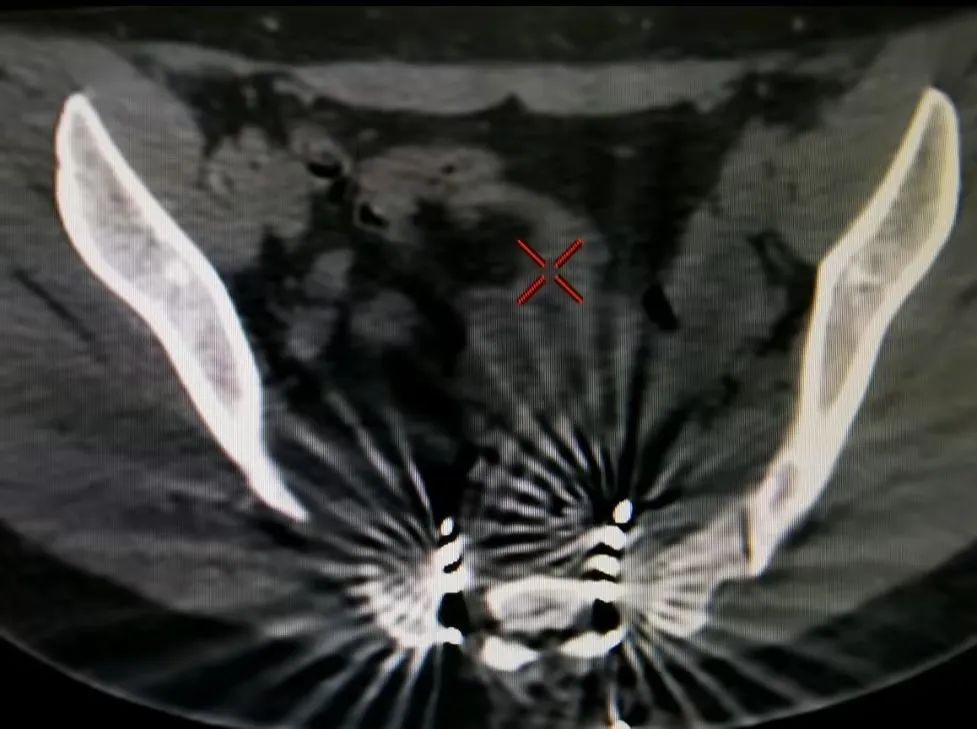

2019年,路桂军组建北京清华长庚医院疼痛团队,针对慢性会阴痛,采取了单病种、多学科诊疗模式,联合我院超声科主任张华斌团队、放射诊断科主任郑卓肇团队,在国内率先开展针对阴部神经的超声、CT三维重建、增强磁共振等相关检查,更精准地诊断疾病、制订治疗方案。

综合评估后,路桂军带领团队为患者行经皮穿刺骶神经电极植入术,术后经过调控患者症状明显改善,顺利出院。